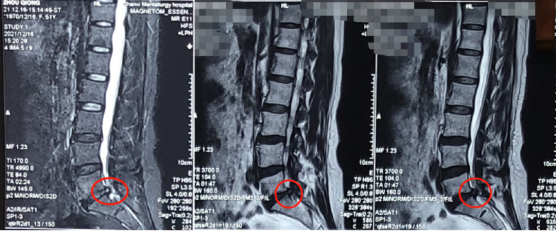

熊东主任接诊后,结合赵女士的查体及其他各项检查结果,确诊她为“腰椎间盘突出症(腰5骶1)”。赵女士在腰5骶1处已经出现比较严重的突出且已压迫到神经,而且症状严重影响生活,建议进行椎间孔镜手术微创治疗。

术前影像学资料

在严格执行相关收治程序后,将赵女士收治入院,并为其尽快安排了椎间孔镜手术治疗。手术由熊东主任亲自操作,在内镜下精细操作,成功摘除了突出的椎间盘组织。术后,赵女士的右腿疼痛明显缓解了,第二天就可以下床走路,和术前走路的样子相比判若两人。